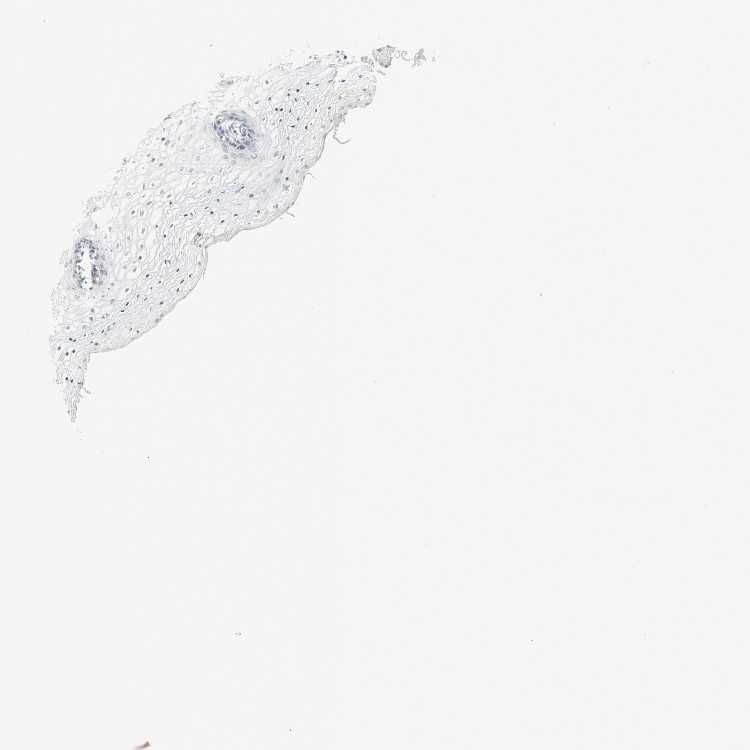

VAGINA - Antibody stainingi

Antibody staining in the annotated cell types in the current human tissue is reported as not detected, low, medium, or high, based on conventional immunohistochemistry profiling in selected tissues. This score is based on the combination of the staining intensity and fraction of stained cells.

Each image is clickable and will lead to virtual microscopy that enables deeper exploration of all samples and also displays staining intensity scores, fraction scores and subcellular localization as well as patient and tissue information for each sample.

Antibody HPA007865Antibody CAB025862

Squamous epithelial cells Not detectedNot detected